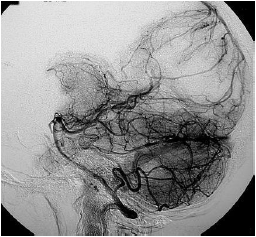

A angiotomografia digital cerebral demonstra a fase

Provas